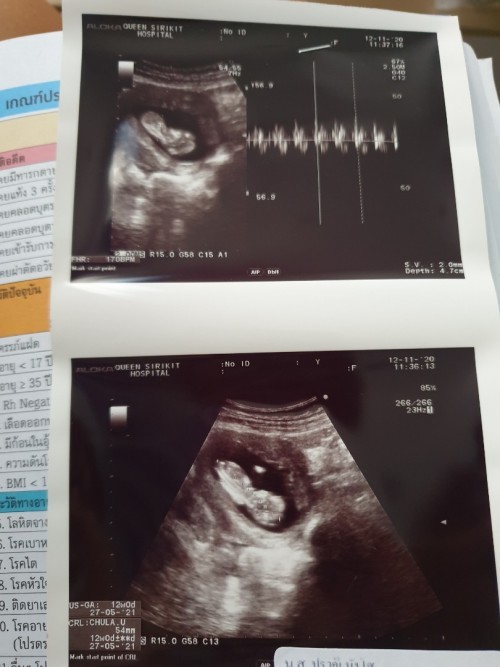

11สัปดาห์ เป็นตัวแล้วนะคะ

บ้านนี้ตรวจตอน11วีคค่ะ

12สัปดาห์ เห็นชัดแล้วค่ะ

บ้านนี้ 13wคะ เป็นตัวแล้ว